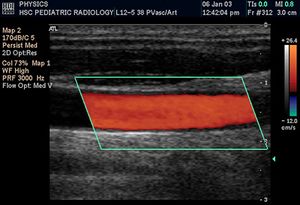

التخطيط الصدى الدوپلري

تكون الصورة عادةً ملونة، فيظهر الدم اما بلون أحمر أوأزرق حسب اتجاه الجريان بالنسبة للمجس الفاحص. ويقدم الجهاز معلومات ممتازة في تقييم صمامات القلب وارتفاع الضغوط الدموية في الأوعية الدموية.

| الجهاز القلبي الوعائي | To assess patency and possible obstruction of arteries Arterial sonography, diagnose DVT (Thrombosonography) and determine extent and severity of venous insufficiency (venosonography) | Intravascular ultrasound |